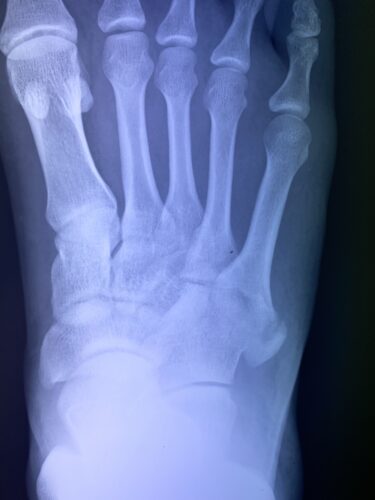

第5中足骨基底部骨折でお悩みの方へ(下駄骨折)の総合ガイド|当院が実践す…

第5中足骨骨折の1症例について